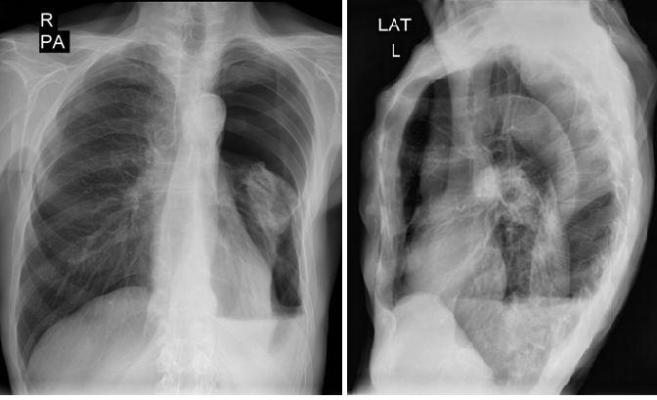

Диагностика плеврального выпота: что нужно знать